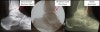

MRI에서 경도의 관절액 저류와 활막 증식이 확인될 수 있습니다.

관절경으로 경비간이나 내과, 외과와 거골활차 사이에 활막이 삽입된 것을 확인할 수 있습니다.

MRI : 발목 충돌증후군(Anterior impingement)

MRI : 발목 충돌증후군(Posterior impingement)